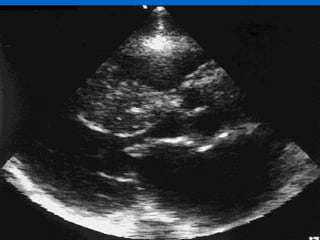

Stem Cells trial Shows Promise

 -11/6/2012 AHA Encouraging two-year follow-up from the Stem

Cell Infusion in Patients with Ischemic

Cardiomyopathy (SCIPIO) trial

 -Echocardiography showed the average LVEF in the 18 patients

infusion to 36.0% (p <0.001) four months after the procedure.

During that period, LVEF improved only from 29.2% to 29.4% in

13 control patients.